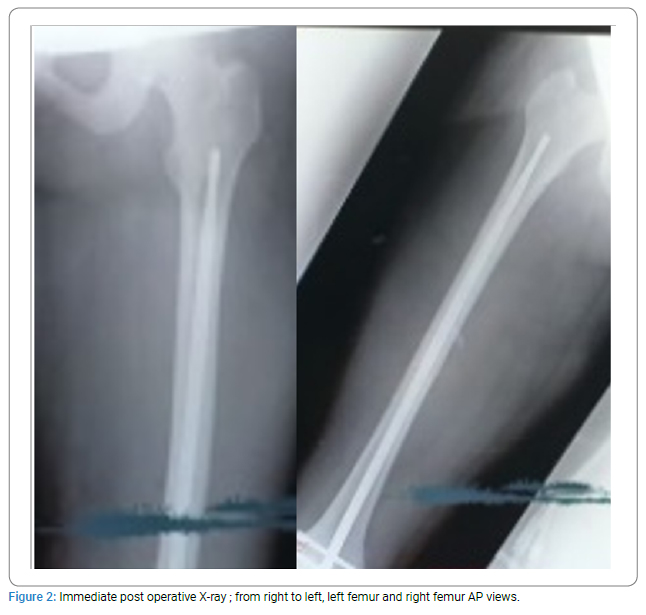

Retrograde intramedullary nailing (with stainless steel SIGN-Fin nails; (Figure 1,Figure 2) of the left and right femurs was done. The left tibia was nailed with a stainless-steel standard SIGN nail (Figure 3,Figure 4). The right femur, which was a closed fracture, was operated on first, then the left femur, and then the left tibia. All fractures were reduced open, avoiding the use of radiation. All fractures were reduced open, preventing the use of radiation.

Total surgery time was eighty-two (82) minutes with an estimated blood loss of 350 mLs. One unit of blood was given immediately post-surgery.

Surgery was Uneventful. Fetal heart Rate checked immediately post-surgery was 142 bpm and regular. No contractions were noticed.